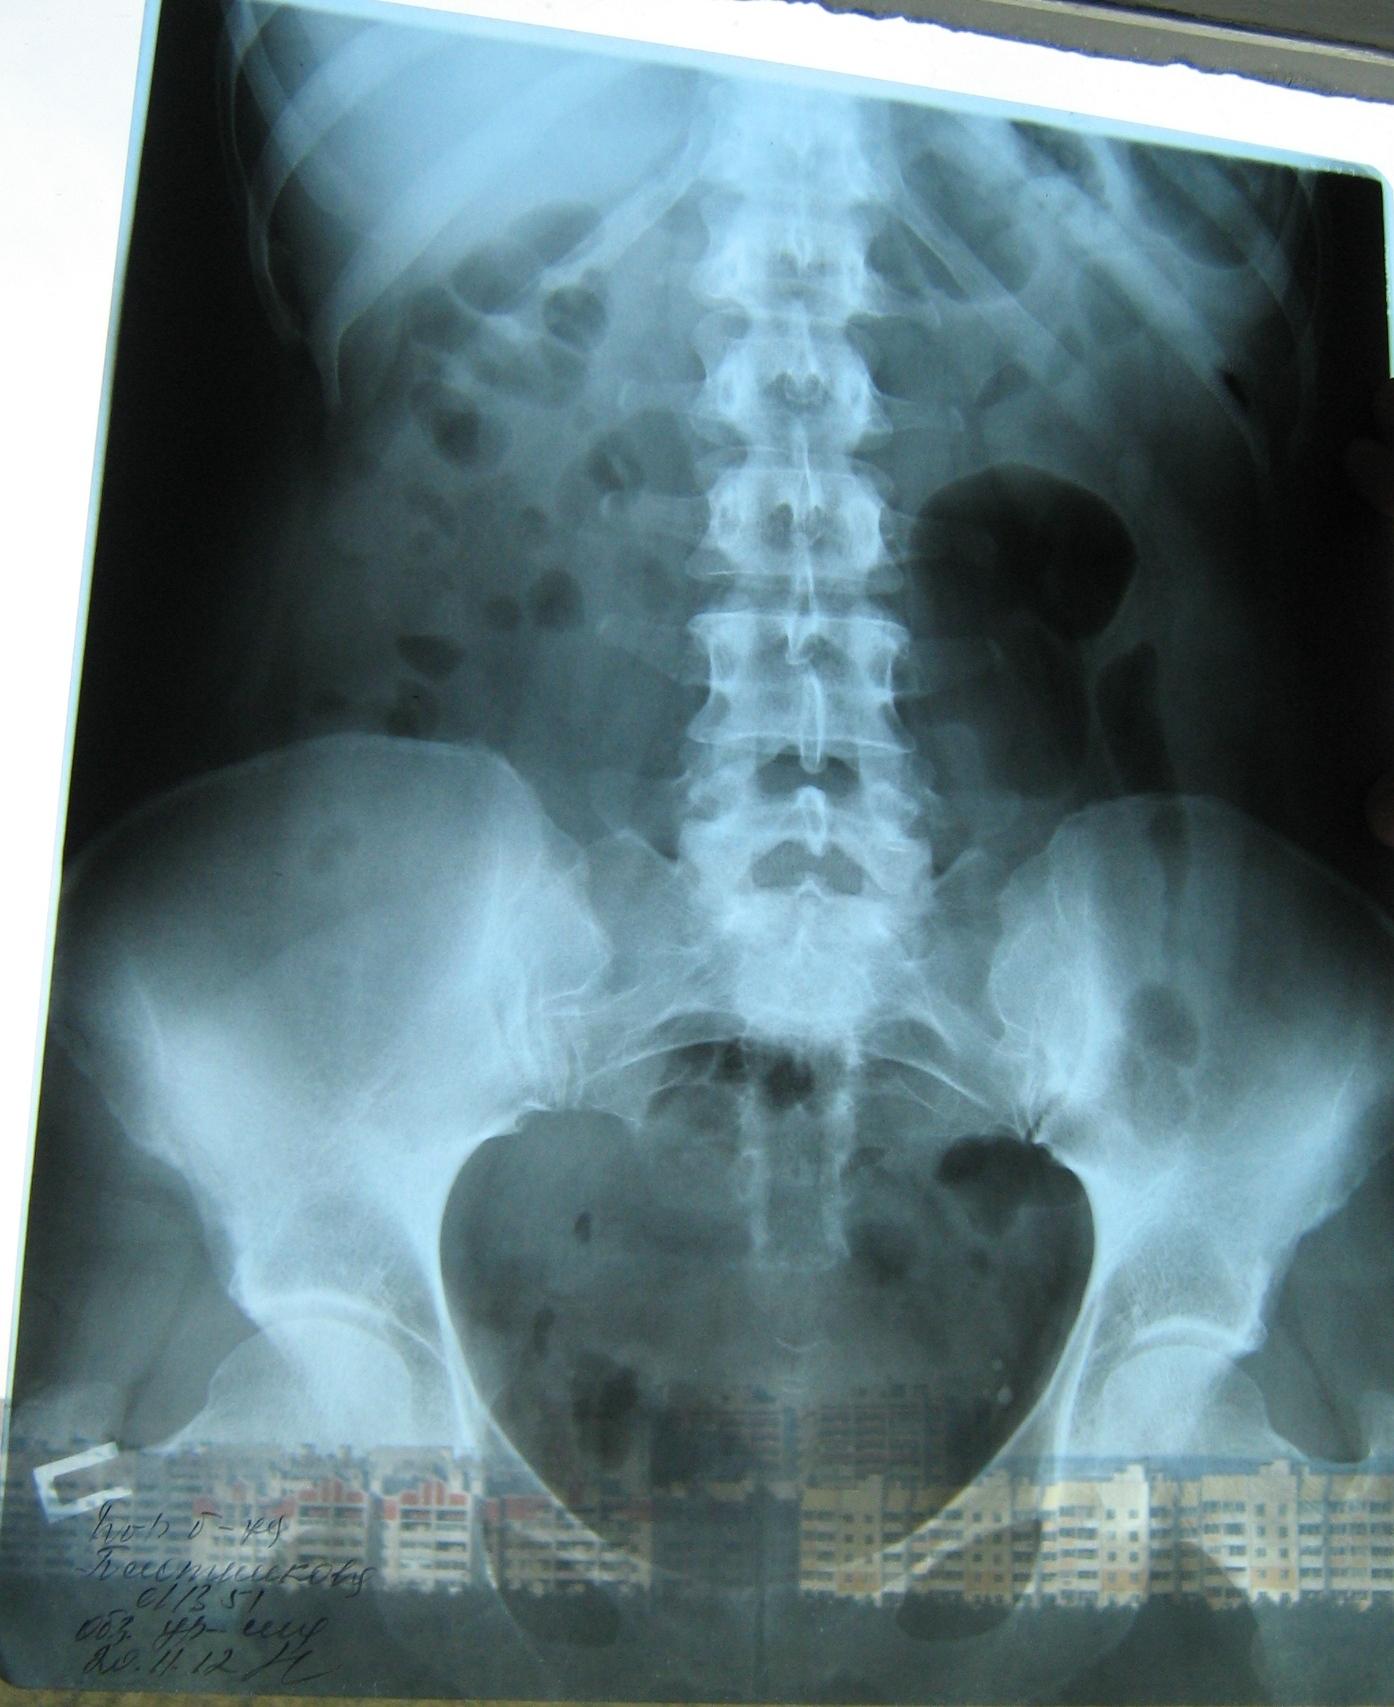

Была сделана операция 04.07.2012г по поводу нефропексии правой почки поясничной мышцей с помощью разреза. После операции болит правая сторона живота и в спине и в пояснице был затронут нерв, и до сих пор правая нога до колен не отходит спереди и сбоку. Через полтора месяца после операции образовался отек, пошло воспаление сзади на спине, потому что был затронут нерв. Сделала урографию через 4 месяца после операции. Если вас не затруднит, посмотрите пожалуйста снимки, правильно ли располагается мочеточник правый после операции. Скажите пожалуйста, посмотрев мои снимки, правильное ли расположение мочеточника и почему болит правая сторона живота все это время, и каким исследованием теперь после операции проверить что там творится в животе, что там затронуто? Все указывает на то что был затронут нерв, оперирующий врач говорит что не может быть такого, а я уже почти всю ногу правую не чувствую

Снимки прикрепляю

Абсолютно нормальное расположение почки и мочеточника . Но ведь и онемение нижней конечности с положением почки не связано. Есть такое понятие "футлярный синдром"- после вынужденного положения конечности. Проконсультируйтесь с неврологом.